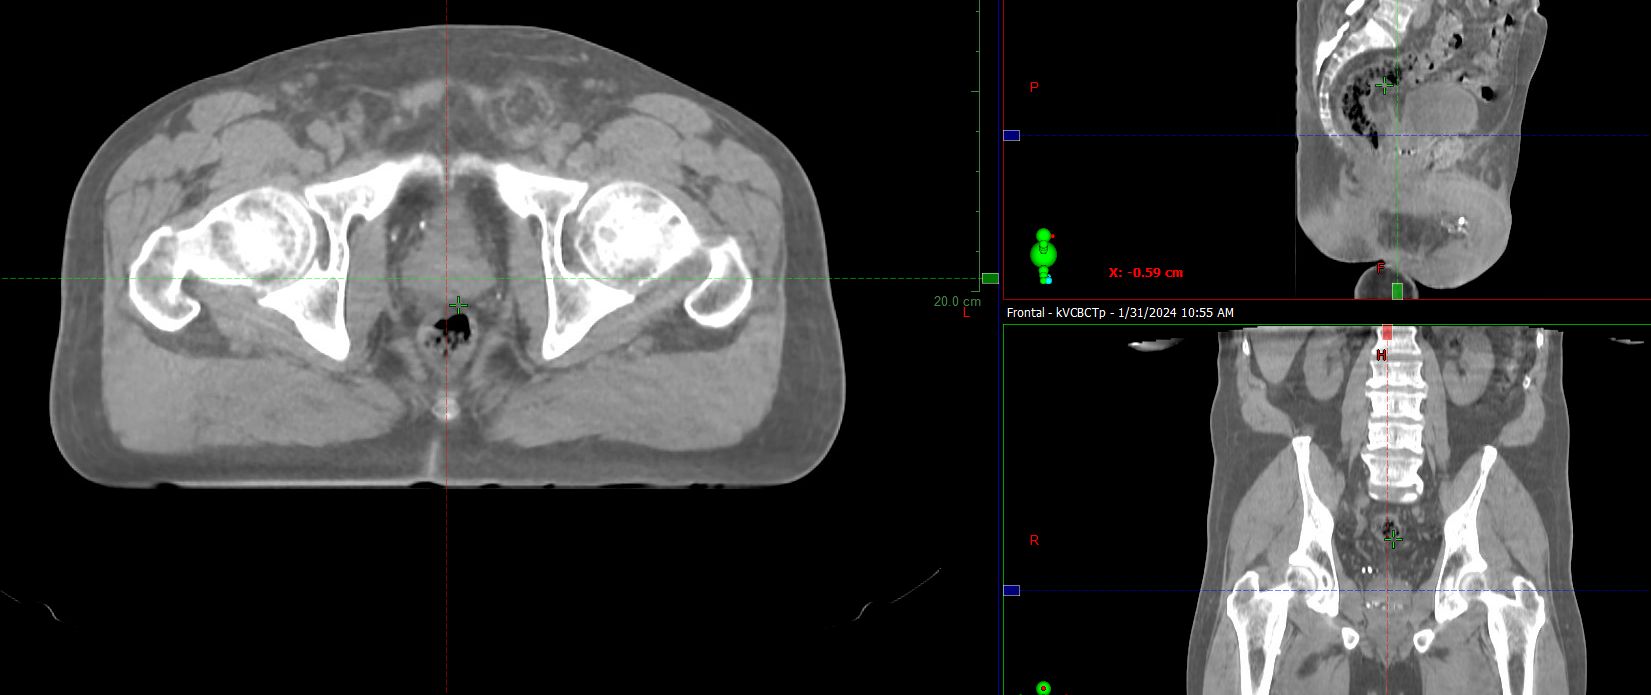

HyperSight brings fast, highly accurate imaging into the treatment room. It enables the acquisition of cone-beam CT (CBCT) images in as little as six seconds, with the Hounsfield Unit (HU) accuracy required for calculating dose distributions directly on the images. The HyperSight image reconstruction algorithms, combined with the expanded field of view (FOV) offer improved visualization of larger areas of interest often encompassing the entire target volume and surrounding organs at risk (OARs). HyperSight is now available as an optional feature on Varian’s Halcyon, Ethos, TrueBeam, and Edge radiotherapy systems.

HyperSight images show how radiotherapy treatment and physiological processes such as weight loss are impacting the tumor and surrounding anatomy over a course of treatment. The enhanced-quality HyperSight CBCT images generated right in the treatment vault make it possible to more easily compensate for any changes to the tumor and nearby organs. Previously, processes for adapting to such changes often required a new CT scan on a separate machine.

“The quality of HyperSight images means that, if we see a concerning change on the CBCT image, we can re-simulate the patient on the fly and then replan, without having to take them off the treatment machine and upstairs to Radiology for re-simulation,” said Dr. Danish. “That has been a real advantage because we treat a high volume of head and neck cases, many of whom need re-simulation multiple times during their course of treatment.”

A dedicated CT scanner for Radiation Oncology is in the plans, but in the meantime, as needed, HyperSight CBCTs are used for treatment planning. “In a hospital system where we have limited resources and space, we want to offer the best care we can by optimizing our internal department procedures. HyperSight is a great solution for us, so that we aren’t completely dependent on Radiology,” says Alvin Khan, PhD, DABR, Director of Clinical Physics. “It has improved our throughput and our clinical staff experience.”

Like St. Joseph’s Medical Center, the Icon Cancer Centre Holmesglen also relies on the hospital CT scanner. “The Radiology Department is very busy because they also handle emergency patients, so we have limited access to the CT scanner,” says Hauville. With no footprint for a diagnostic CT scanner dedicated to radiation oncology, Icon Holmesglen upgraded its Halcyon system with HyperSight imaging in March 2023. This upgrade gave the Icon clinical team the ability to simulate and plan for prostate, rectum, and gynecological treatments in their own department. “Since we started utilizing HyperSight for planning, our clinicians have been very satisfied with the ability to accurately contour volumes and calculate dose distribution on the images,” reports Peter Phung, Senior Medical Physicist.